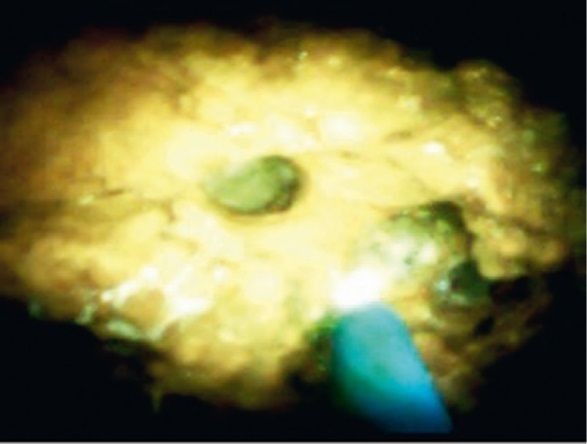

С использованием системы Spyglass (Boston Scientific, Марлборо, Массачусетс, США), проведенной через инструментальный канал дуоденоскопа (Olympus TJF160, Токио, Япония), удалось визуализировать конкремент. Литотрипсия проводилась с применением гольмиевого лазера (Auriga QI, Boston Scientific) мощностью 800 мДж, затем 1200 мДж и частотой 4 Гц, затем 6 Гц (рис. 2).

Рисунок 2 [1].